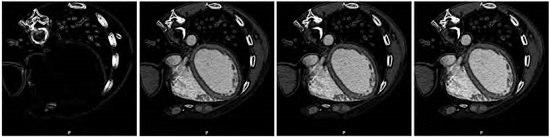

Figure 5 shows the results obtained after performing the experiment associated with S2 strategy. Each image is associated with each case (main, residual1, residual2 or full). The neighborhood space used is n = 4.

Meanwhile, when visually inspecting the results obtained from medical data, we observed that the components of our similarity-based image enhancement technique allow us to emphasize, to sharp, and to smooth medical image features, which facilitates the development of a solution to the problem of the medical image segmentation. The images of the first column of the Figure 5 show the utility of the component main to detect the edges of the anatomical structures located in a computed tomography slice of the thorax for both proposed strategies, S1 and S2. The remaining images of the Figure 5 show how the other components enhance the MSCT slice.

Comparing the values of the Tables 3-4, we observe that the score function, for both strategies S1 and S2, is higher if a neighborhood of n = 4 is considered when the component residual1 is used. In fact, the score function for S1 is better than score function for S2. Additionally, it can be seen that the minimal score in both S1 and S2 strategies is yielded for component main considering n = 4 as neighborhood size.

Reopening the issue of visual inspection, the local structures information (edges) of the original image is very well preserved in the processed image with minimal score function (images of first column of Figure 2, and first images on Figure 4-5). In fact, the component main of the criterion can be thought of as an edge detector operator. The score function associated to image processed with the component main in S2 strategy is significantly lower than the obtained with S1 strategy and the dispersión associated with this minimum average value is also low and it is 2.11%. This is because the main in S2 is linked to a IHPF generated using an edge detector.